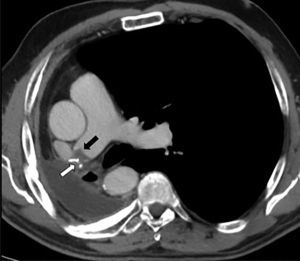

PET was diagnosed in 10 cases (2.1%) and AST in 9 (1.9%) (Fig. 2), resulting in an incidence of 1.9 cases of suture thrombosis per 100 patients operated. Table 2 shows surgical, radiological and oncological data by patient groups. Median follow-up after surgery was 49.4 months (interquartile range 34.8–70.1 months), and 147 deaths were documented. Table 3 describes causes for death by patient groups.

After surgery, median time until AST was visualized was 11.3 months (interquartile range 2.7–42.2 months) with a range of 67.5 (1.4–69.0 months); of the 9 cases, 5 (56%) occurred within the 12 months following surgery. Seven (78%) of the AST patients began antiplatelet treatment. Three patients (33%) died, 2 of whom were receiving antiplatelets. Of these, 1 had a lymphoproliferative disorder, and 1 had an acute subdural hematoma while also receiving chemotherapy for tumor relapse. Median duration of antiplatelet treatment was 298 days (interquartile range 45–532 days). Filling defects were resolved, according to radiological findings, in 6 cases (67%), 2 of which were not receiving antiplatelets (22%). Media time to resolution was 12.9 months (interquartile range 3.8–20.3 months). Mean number of CTAs performed during follow-up of AST patients was 11.7±6.3 CTAs, statistically higher than the mean in patients without AST or PTE, who had 6.9±4.9 CTAs (P=0.02).